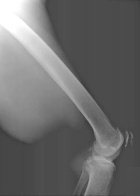

68 year old male with mass noted in left leg four weeks ago

Zoom image: Radiological image Radiological image.